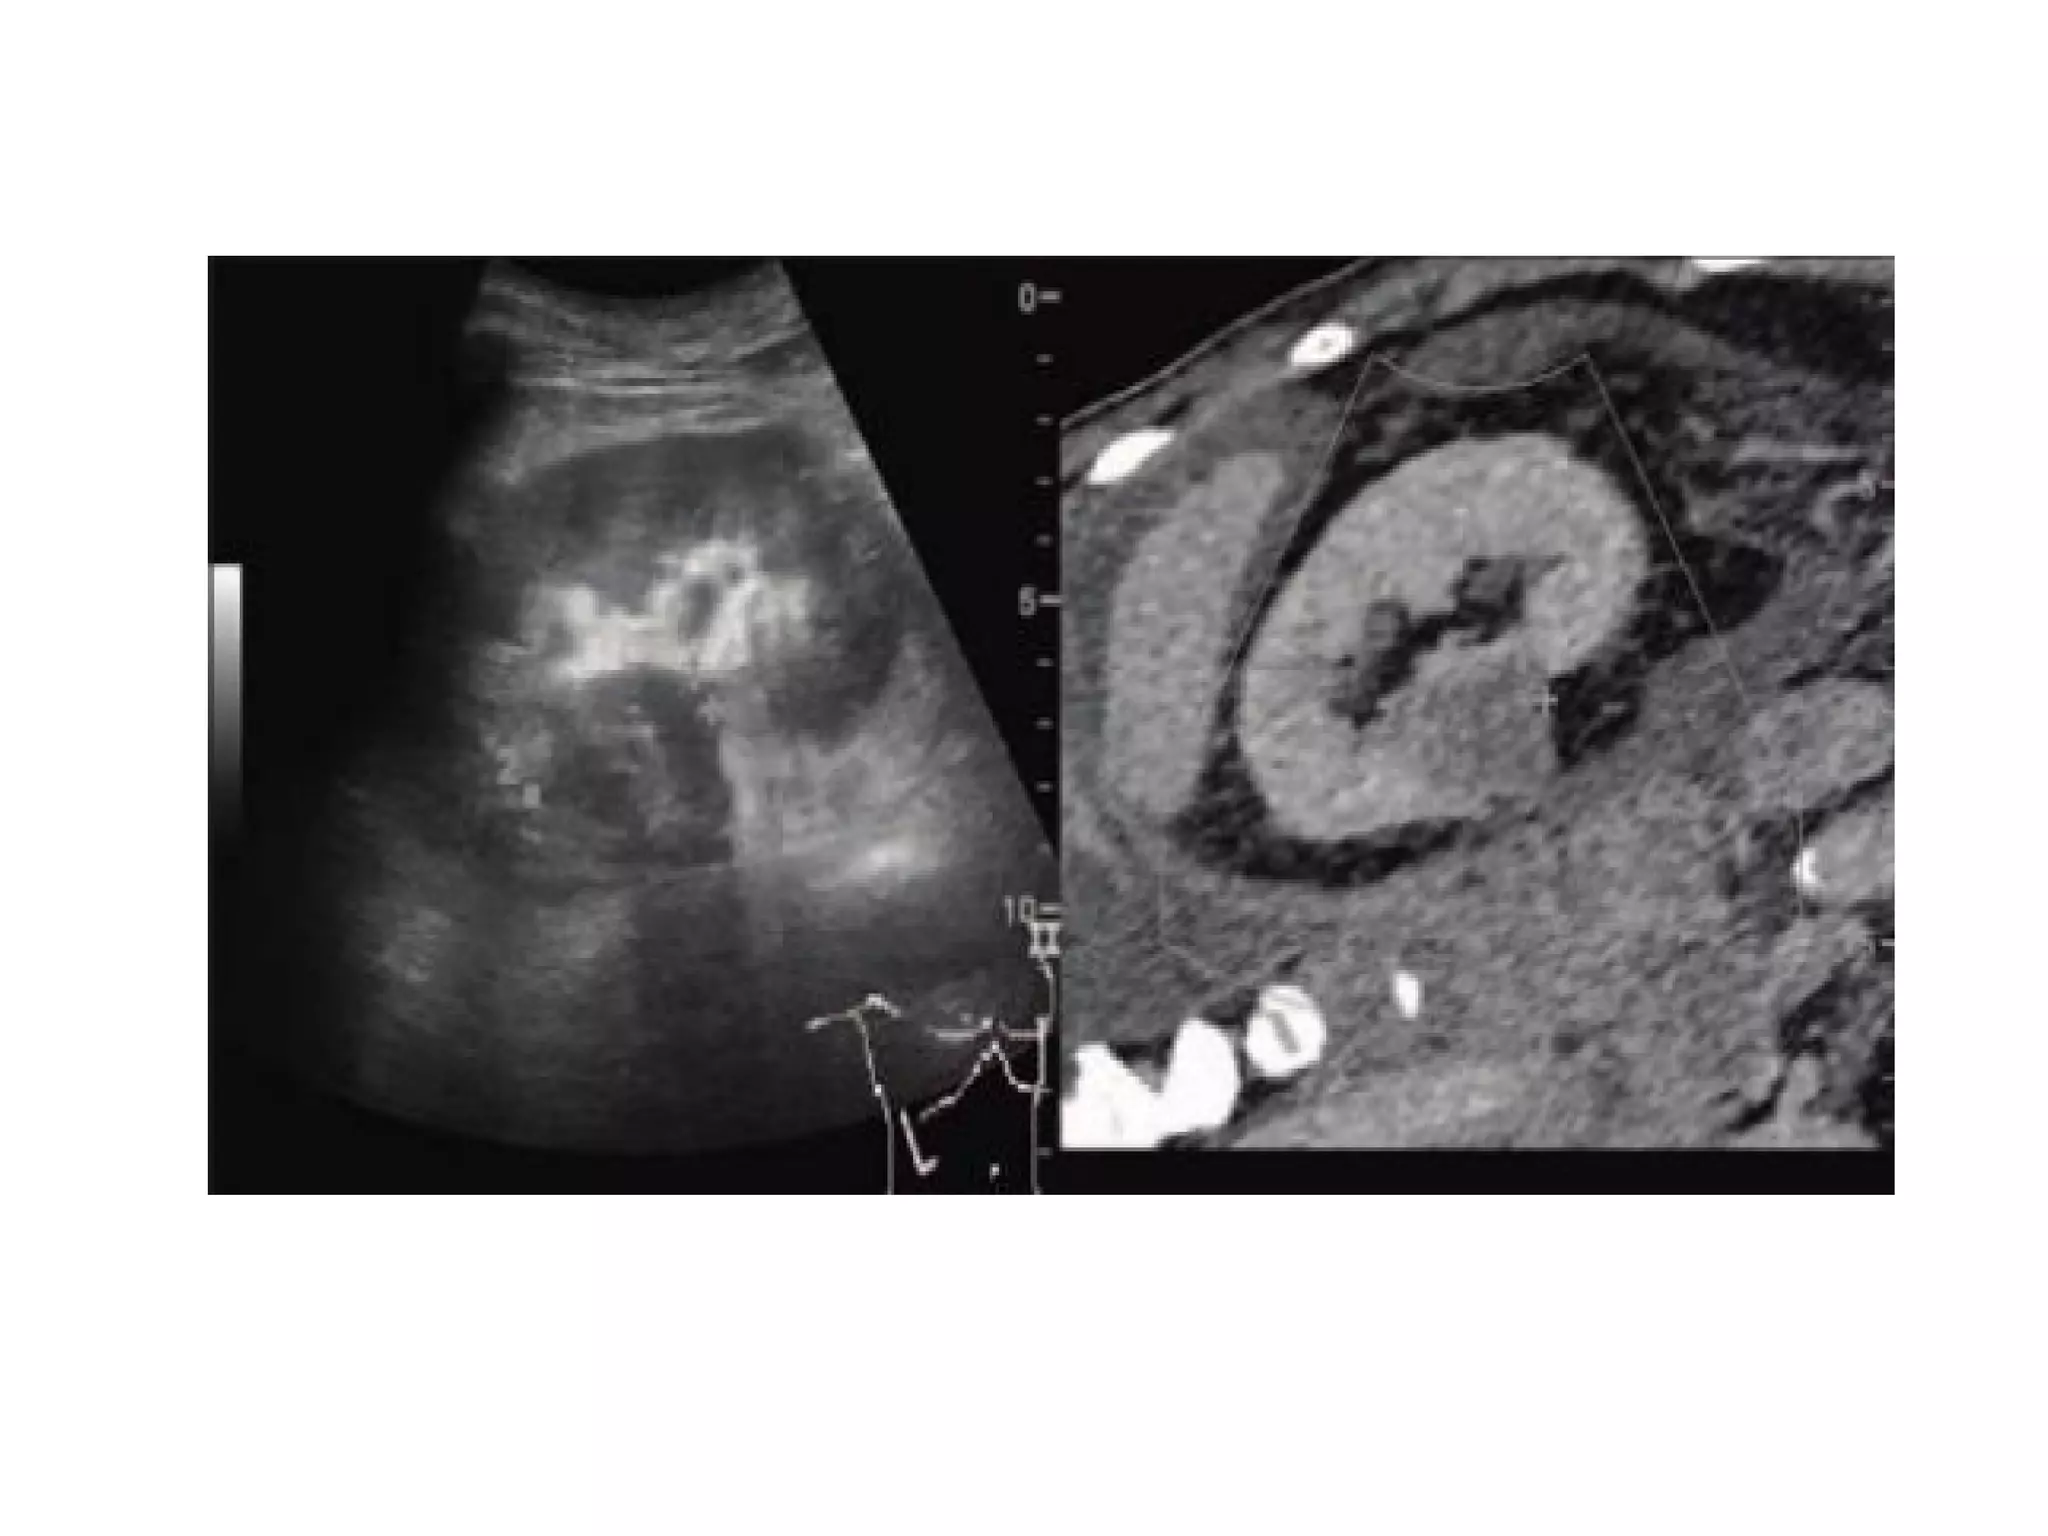

FUSION IMAGING

• Fusion imaging or hybrid imaging means

combination of two imaging techniques.

• This can be in the form of ultrasound with MRI

or CT

• or it can be fusion of (ultrasound, CT or MRI)

with molecular imaging technique like SPECT or

PET

The advantages of incorporating ultrasound in image

fusion consist in the :

• real-time images (which enable image-guided

intervention),

• the lack of radiation to both patient and staff,

and

• the possibility of comparing findings on one

modality with another modality .

Software for fusion of real-time ultrasound images

with CT, MRI, or PET/CT is incorporated in several

high-end ultrasound systems.

STEPS OF FUSION

• During examination ultrasound screen is seen as split images

with virtual reconstructed CT/MR image on one side and

currently acquired USG image on other side of the screen.

• An attempt is made to match these two images with each

other using some clearly visible anatomic landmark (e.g.

portal vein bifurcation, superior most margin of kidney or

the lesion itself, etc.)

• For fusion imaging variety of tracking methods are used,

common are the optical tracking system and

electromagnetic tracking system.

Clinical applications

• Isoechoic lesions not well appreciated on grey

scale.

• Previously ablated lesions with recurrence not

well visualized.

• Interventional treatment is easy.